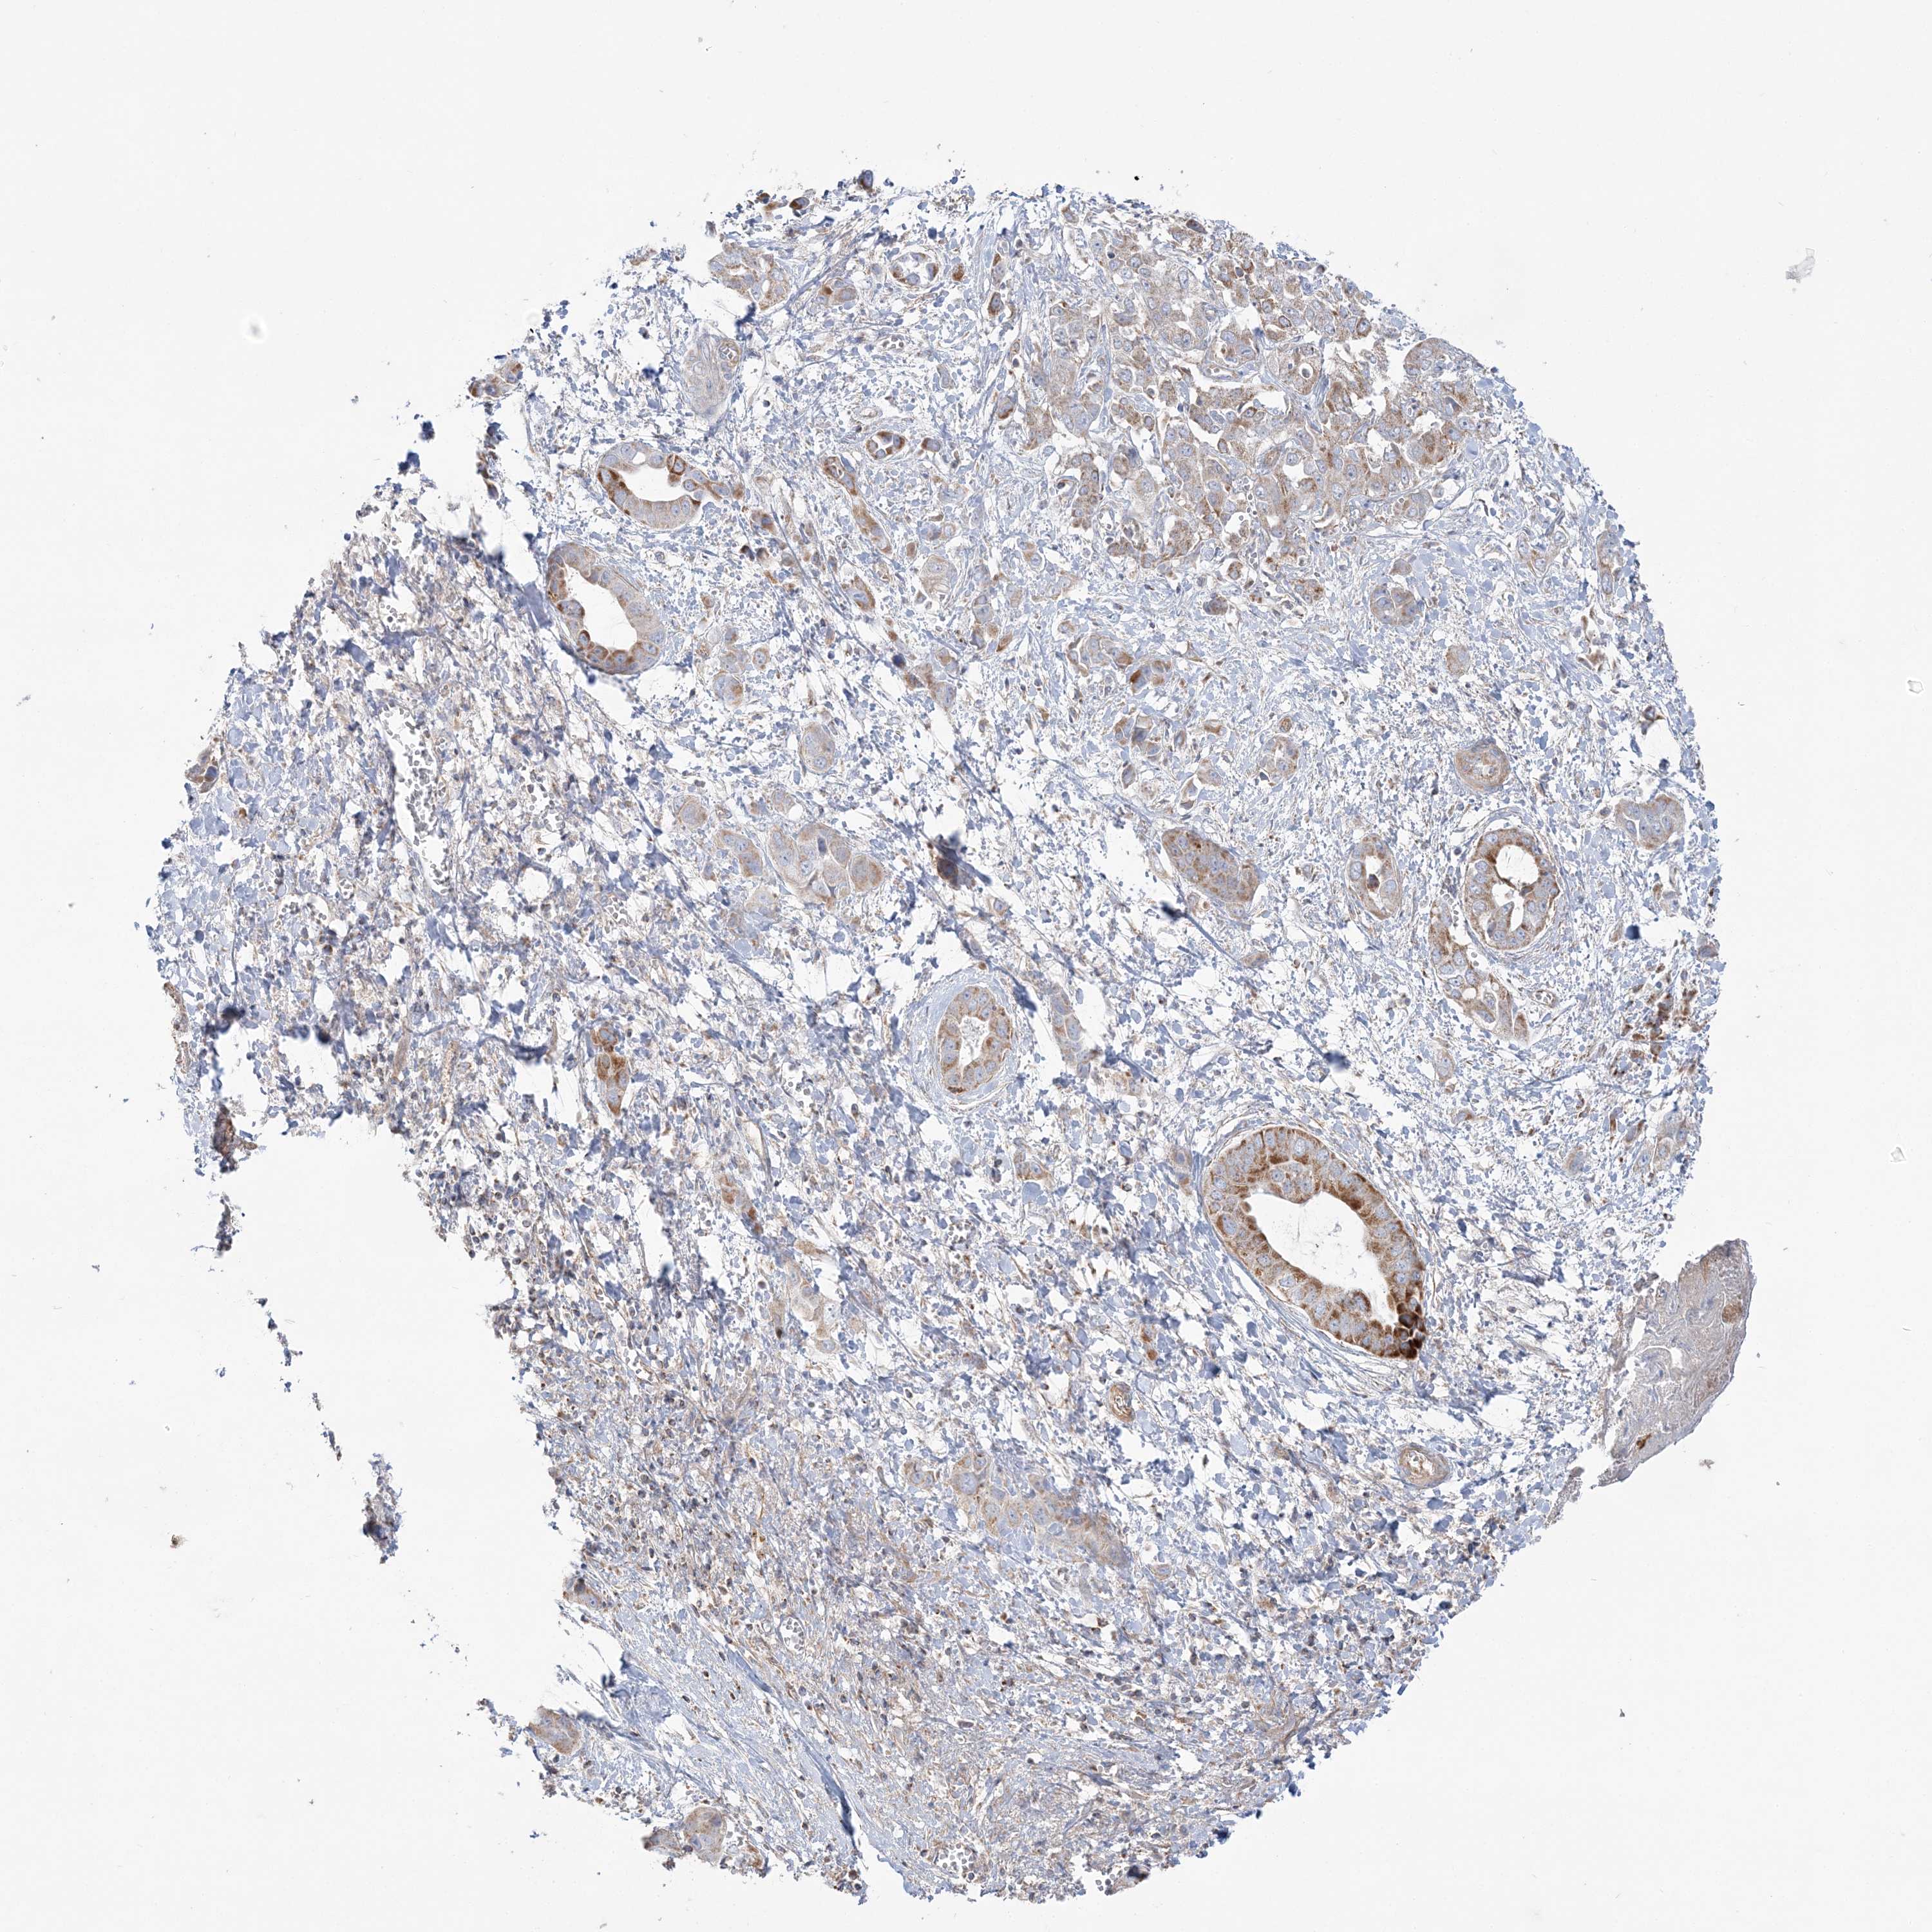

LIVER CANCER - Protein expressioni

A mouse-over function shows sample information and annotation data. Click on an image to view it in a full screen mode. Samples can be filtered based on level of antibody staining by selecting one or several of the following categories: high, medium, low and not detected. The assay and annotation is described here.

Antibody stainingi

Antibody staining in the annotated cell types in the current human tissue is reported as not detected, low, medium, or high, based on conventional immunohistochemistry profiling in selected tissues. This score is based on the combination of the staining intensity and fraction of stained cells.

Each image is clickable and will lead to virtual microscopy that enables deeper exploration of all samples and also displays staining intensity scores, fraction scores and subcellular localization as well as patient and tissue information for each sample.

Antibody HPA036560

Antibody HPA036561

Staining

High

Medium

Low

Not detected

Intensity

Strong

Moderate

Weak

Negative

Quantity

>75%

75%-25%

<25%

None

Location

Nuclear

Cytoplasmic/membranous

Cytoplasmic/membranous,nuclear

Cholangiocarcinoma

Carcinoma, Hepatocellular, NOS